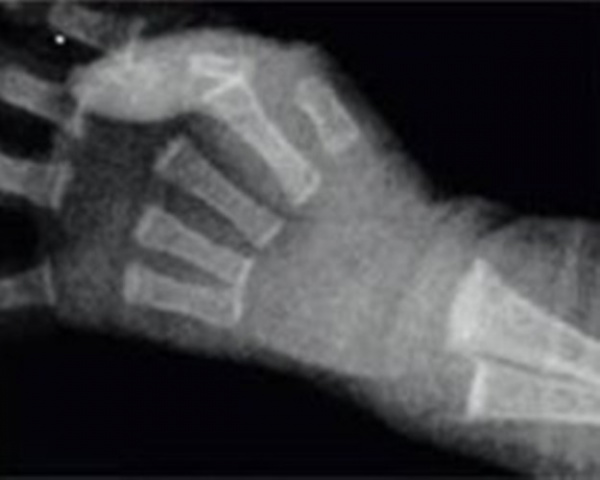

• Рентген костей. Видимые изменения на рентгенограммах определяются снижением плотности костной ткани на 20-40%. Характерные признаки остеопении недоношенного ребенка: «прозрачные» кости, расширенные и неровные края эпифизов, патологические переломы.

Прозрачность костей при остеопении.